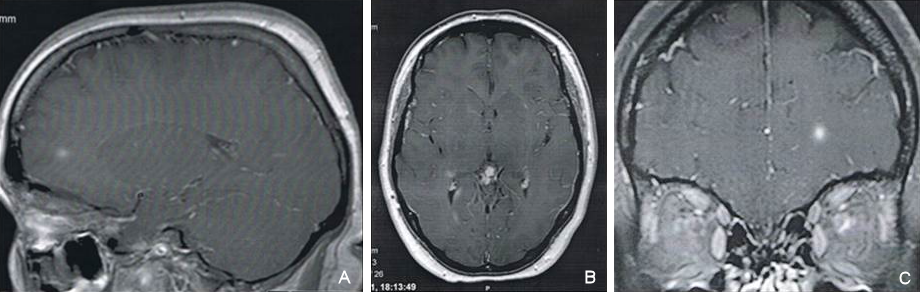

The patient performed in the emergency room a CT and blood tests. On the same day she was admitted to the Neurology Department where she performed MRI (Figure 2 [Fig. 2], Figure 3 [Fig. 3]), lumbar punction with analysis of CSF. More specific tests and chest CT for screening of thymoma were requested. On the next day our patient was seen at the Ophthalmology Department where she made the following imaging tests: optical coherence tomography, angiography, visual fields and electrophysiological tests.

Figure 2: Brain MRI (day 2) (A, B and C) showed small areas of increased signal intensity on left temporal lobe and right periventricular area in cerebral white matter; with gadolinium uptake in the left optic nerve.